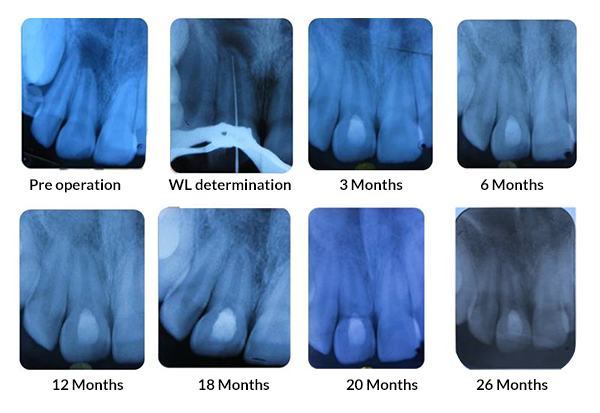

PRF Mediated REP in 21 with 26 Months Follow Up

Complete Bony Healing, Apex Closed, Lateral Dentinal Wall Thickened, PDL Apically